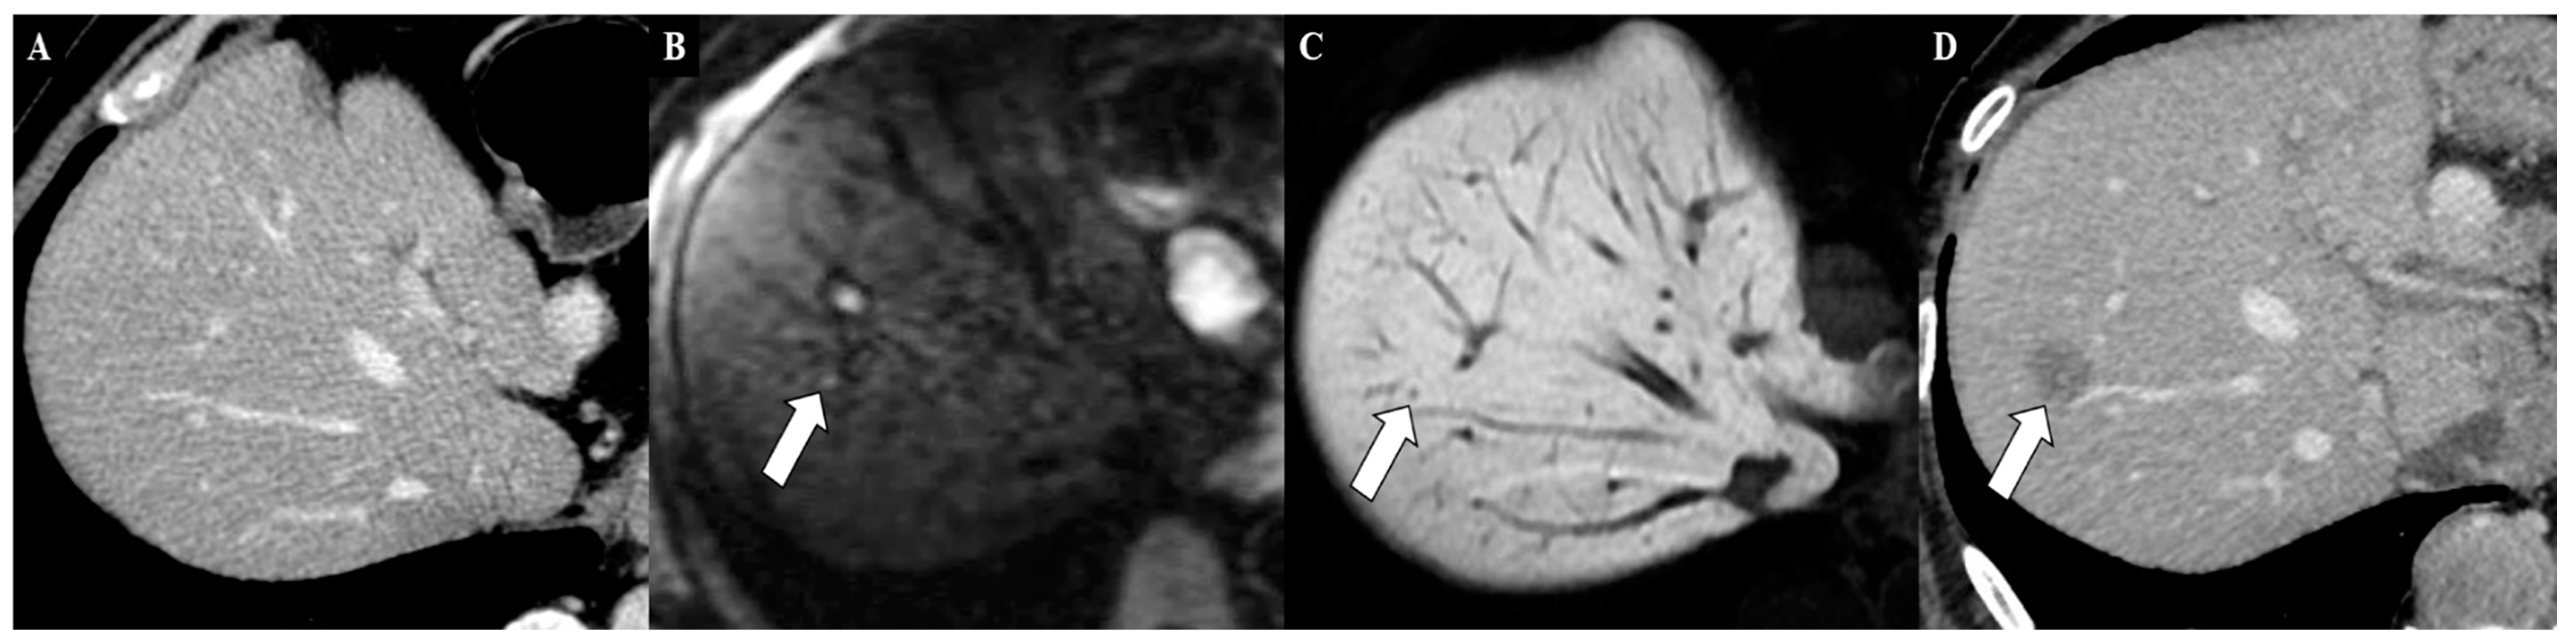

6. Magnetic Resonance Imaging in the Assessment of Liver Metastases from Gastric Cancer